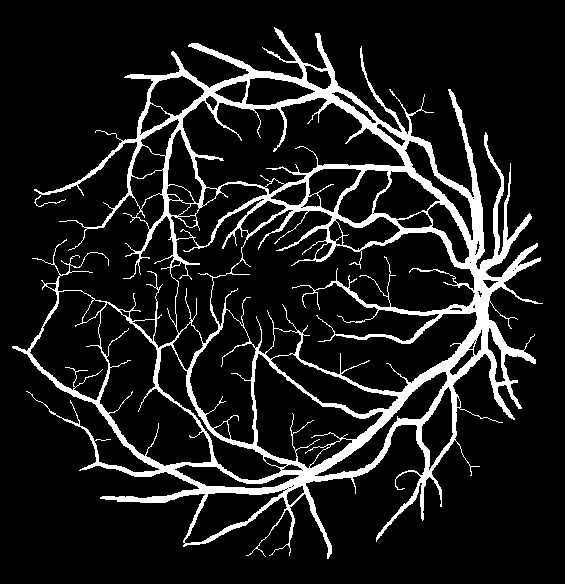

The precise segmentation of thin tubular structures is a critical task across diverse domains in engineering and medical applications (Fig. 1). Topological correctness is fundamental for facilitating downstream tasks such as analyzing blood flow dynamics, delineating neuronal boundaries in Electron Microscopy imagery, evaluating risk factors for vascular pathologies, aiding in surgical planning, and optimizing route planning [21, 1, 32, 40, 6, 5]. Classical approaches for the automated segmentation of thin curvilinear structures have encompassed methods including image transforms [25, 34], mathematical morphologies [41, 29], filtering [13, 10, 15], differential operators [33], among others [8, 16, 19, 3, 2]. Deep learning based techniques have played an increasing role in recent years with standard segmentation networks such as UNet [27] being popular. Standard overlap-based losses (eg. dice-similarity coefficient [43]) enable such networks to segment large structures while often struggling with small elongated ones [18] as shown in Fig. 2.

| DRIVE[32] | 2D | binary | 20 | Blood vessels on retina images |

We employ five public datasets featuring thin structures for validating the proposed Skeleton Recall Loss. The datasets span natural as well as medical images, covering a range of segmentation challenges, including both binary and multi-class segmentation problems in 2D as well as 3D contexts. An overview of the datasets can be found in Tab. 1. Among the three 2D datasets used in this study, the Digital Retinal Images for Vessel Extraction (DRIVE) dataset [32] was employed, focusing on retinal vessel segmentation. Additionally, structural inspection images designed for concrete crack segmentation (Cracks) [36] and aerial images of Massachusetts for road segmentation (Roads) [21] were included, highlighting the diversity of thin structures in natural and constructed environments. In the 3D domain, we incorporated two cutting-edge medical image segmentation challenge datasets. One of them was ToothFairy111https://toothfairy.grand-challenge.org/, which was a segmentation challenge on 3D Cone-Beam CTs [6, 5] featuring the inferior alveolar canal as the target structure. Additionally, the TopCoW222https://topcow23.grand-challenge.org/ dataset for topology-aware 3D segmentation of vessels in the Circle of Willis for CTA and MRA data [40] was utilized, encompassing binary as well as multi-class segmentation on 13 different subtypes of vessels. This diverse set of datasets enables a comprehensive evaluation of the proposed Skeleton Recall Loss, demonstrating generalizability of the method to a wide range of thin structure segmentation challenges in both 2D and 3D contexts.